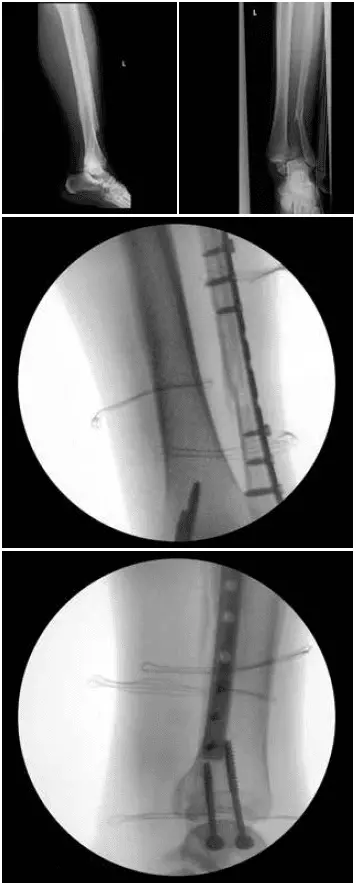

Na rehabilitację trafiła kobieta, lat 25, która w wyniku nieprawidłowego lądowania przy drugim kursie na AFF doznała wieloodłamowego złamania kości strzałkowej lewej, kostki przyśrodkowej i krawędzi tylnej piszczeli. Kończynę unieruchomiono w ortezie typu walker. Wykonano zabieg zespolenia złamania kostki bocznej płytą Medal – mocowana dwoma śrubami korowymi i czterema śrubami blokowanymi. Zespolenie kostki przyśrodkowej dwoma śrubami kostkowymi.